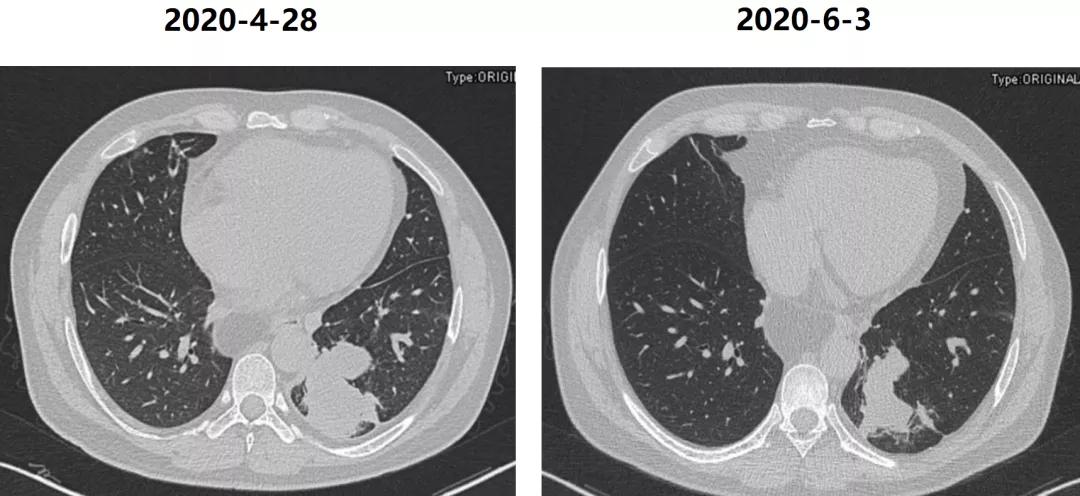

患者出院后口服威凡三周后复查胸部CT左肺下叶病变明显缩小,嘱患者胸外科就诊择期手术。

至此,得出最后诊断:1、肺隔离症(叶内型)伴曲霉菌感染2、左下肺细菌性肺炎;3、高血压2级中危;4.食管裂孔疝。